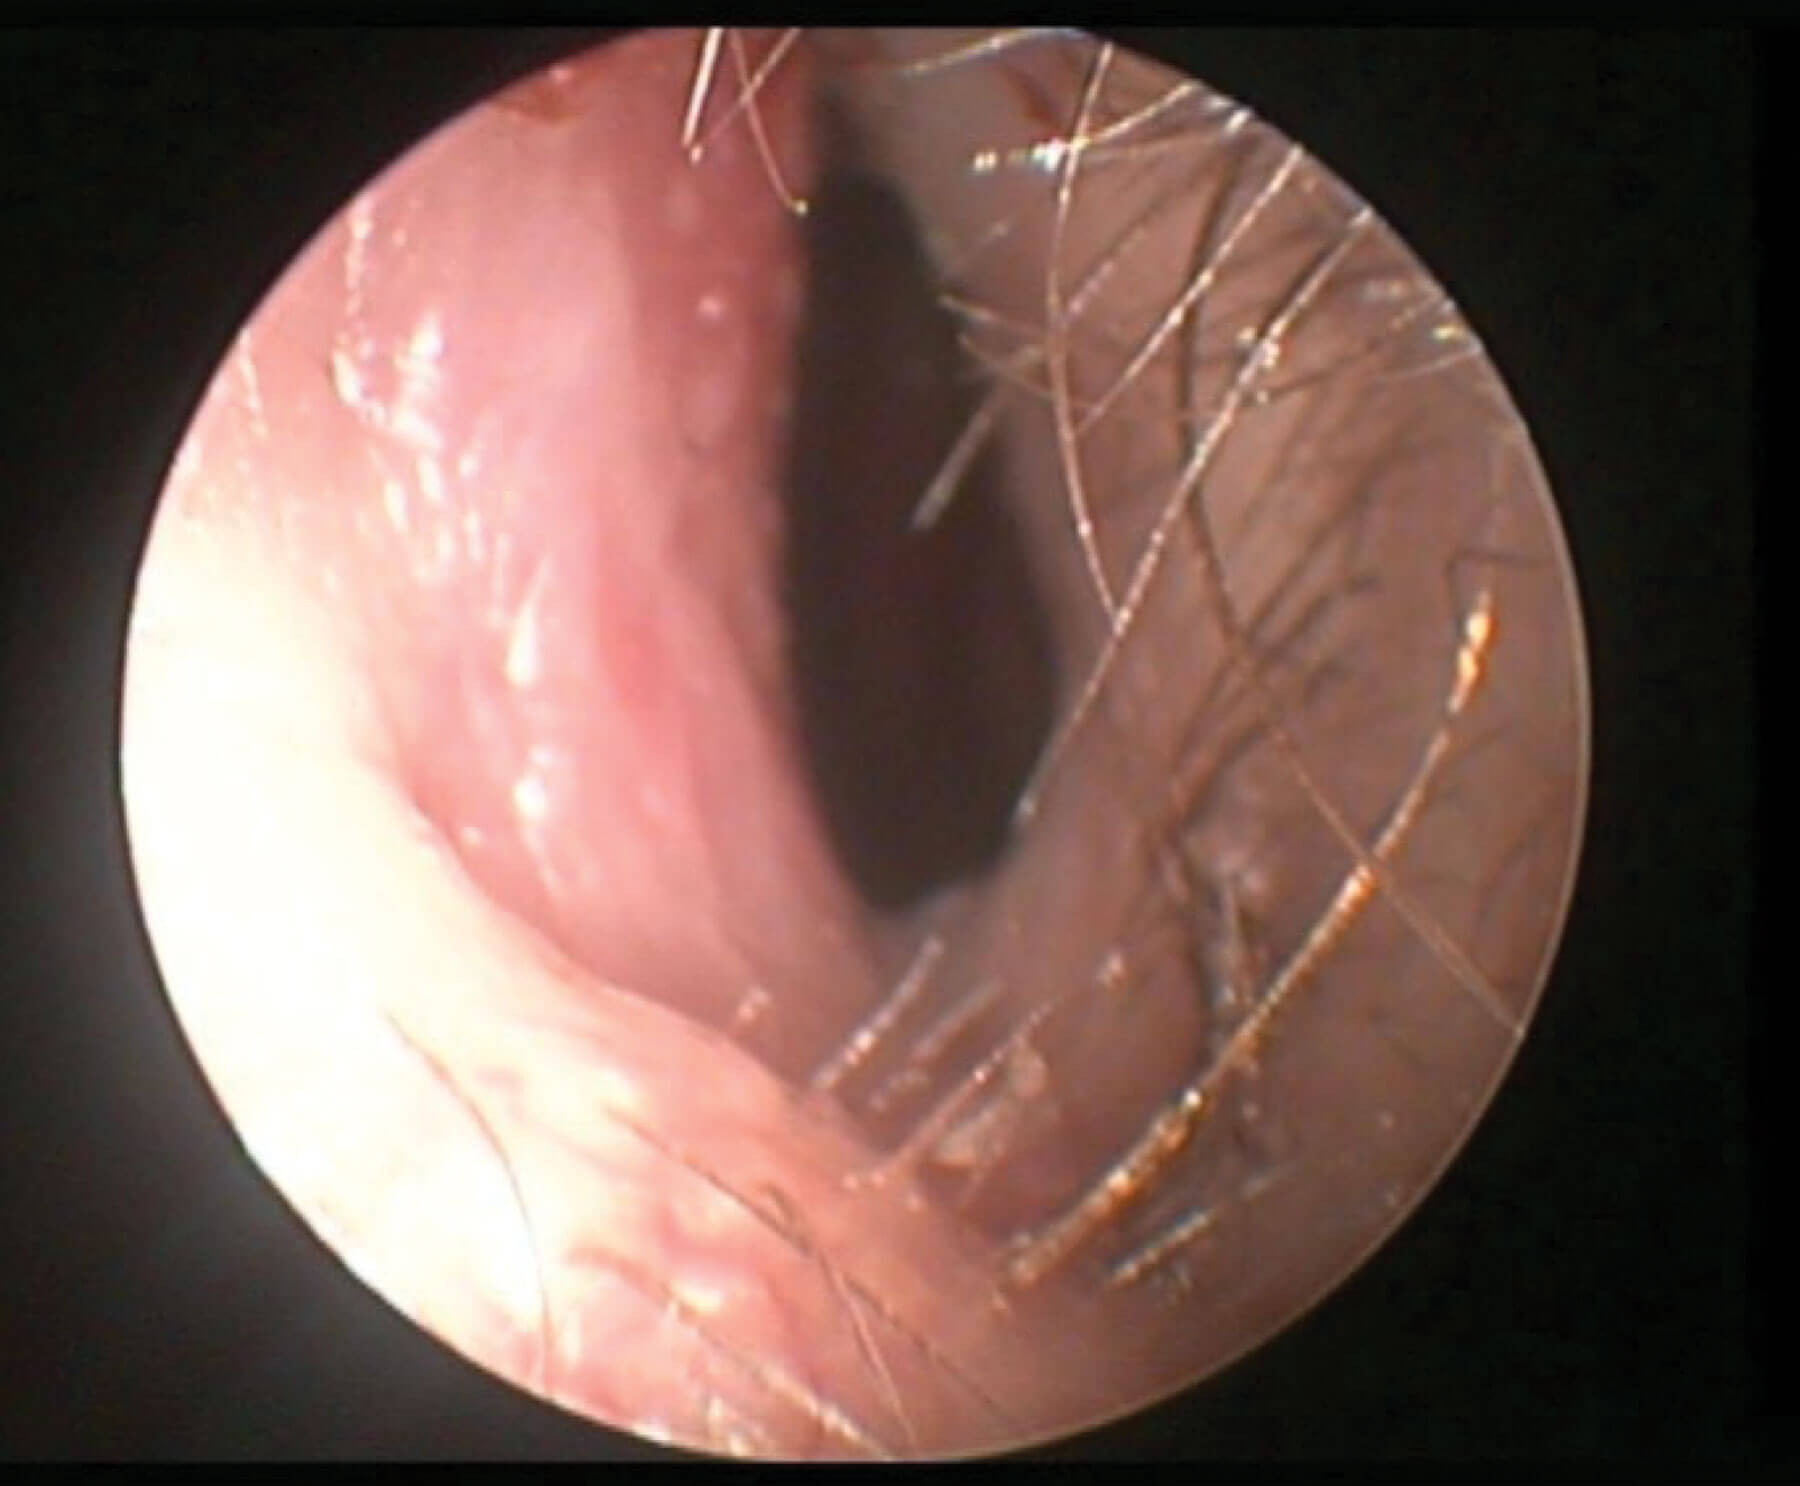

Figure 1: Clinical example of deviated septum into left nostril.